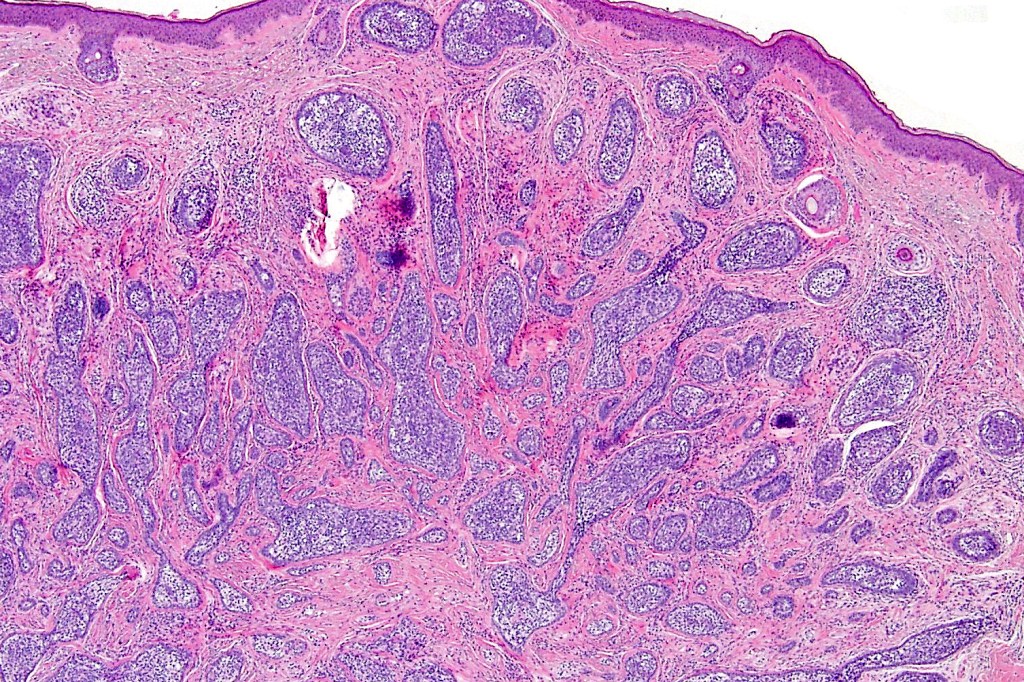

Histological features

•Dermal nodule, rarely extends into subcutaneous fat

•Irregular lobules of epithelial cells embedded in a dense fibrous stroma

•Peripheral rim of darkly staining basaloid cells surrounding larger pale staining cells with vesicular nuclei with often prominent eosinophilic nucleoli

•Admixed lymphocytes (an obligatory feature)

•Germinal centers sometimes present